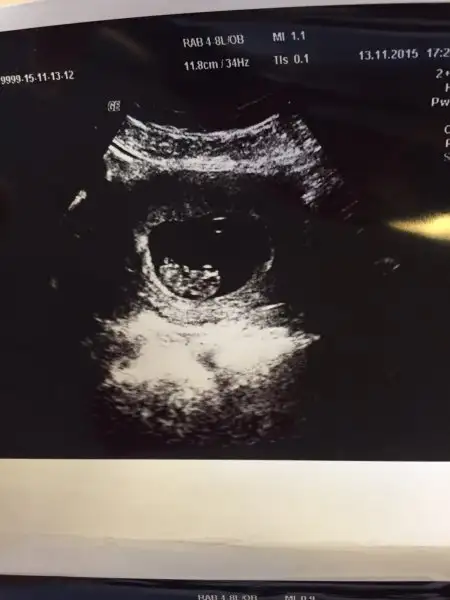

Kızlar cinsiyet tahmininiz var mı bize :)

Eklentiler

• IMG-20151117-WA0002.webp

12,8 KB · Görüntüleme: 91